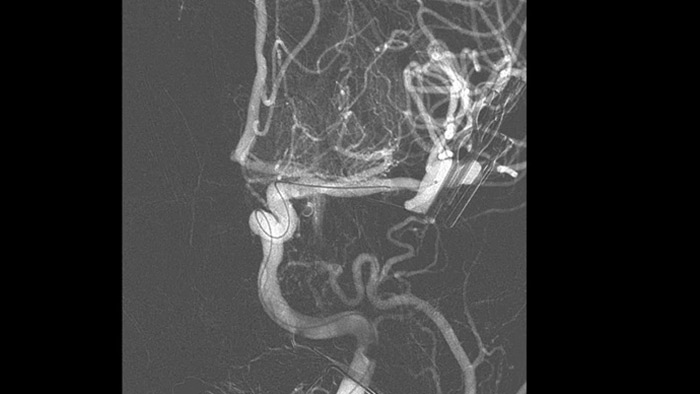

Анатомические ориентиры поддерживают точную 3D-навигацию

Smart CT

Технология SmartCT Roadmap предоставляет данные изображений анатомических структур, обеспечивая точность навигации при проведении к тромбу проводника, катетера и специального устройства.